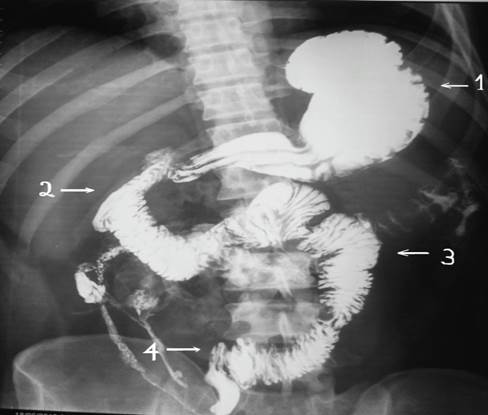

Liquido inflamatorio libre en cavidad, isquemia intestinal masiva desde el duodeno a colon transverso en un paciente (Imagen 1), desde una porción de aproximadamente 15 cms del ángulo de treitz a colon transverso en el segundo paciente (Imagen 2), en el tercero encontramos gangrena intestinal desde 10 cms del ángulo de treinta hasta la mitad del colon transverso derecho (Imagen 3).

Ilustración 3 Gangrena intestinal masiva

Fuente: Hospital de Especialidades Guayaquil “Doctor Abel Gilbert Pontón”.

Autor: Dr. Fernando Moncayo A.

Se verifico el tránsito corto mediante estudio de tránsito baritado intestinal (Imagen 7,8.9)

Ilustración 9 Tránsito gastro-intestinal, muestra anastomosis yeyuno-colónica izquierda baja.